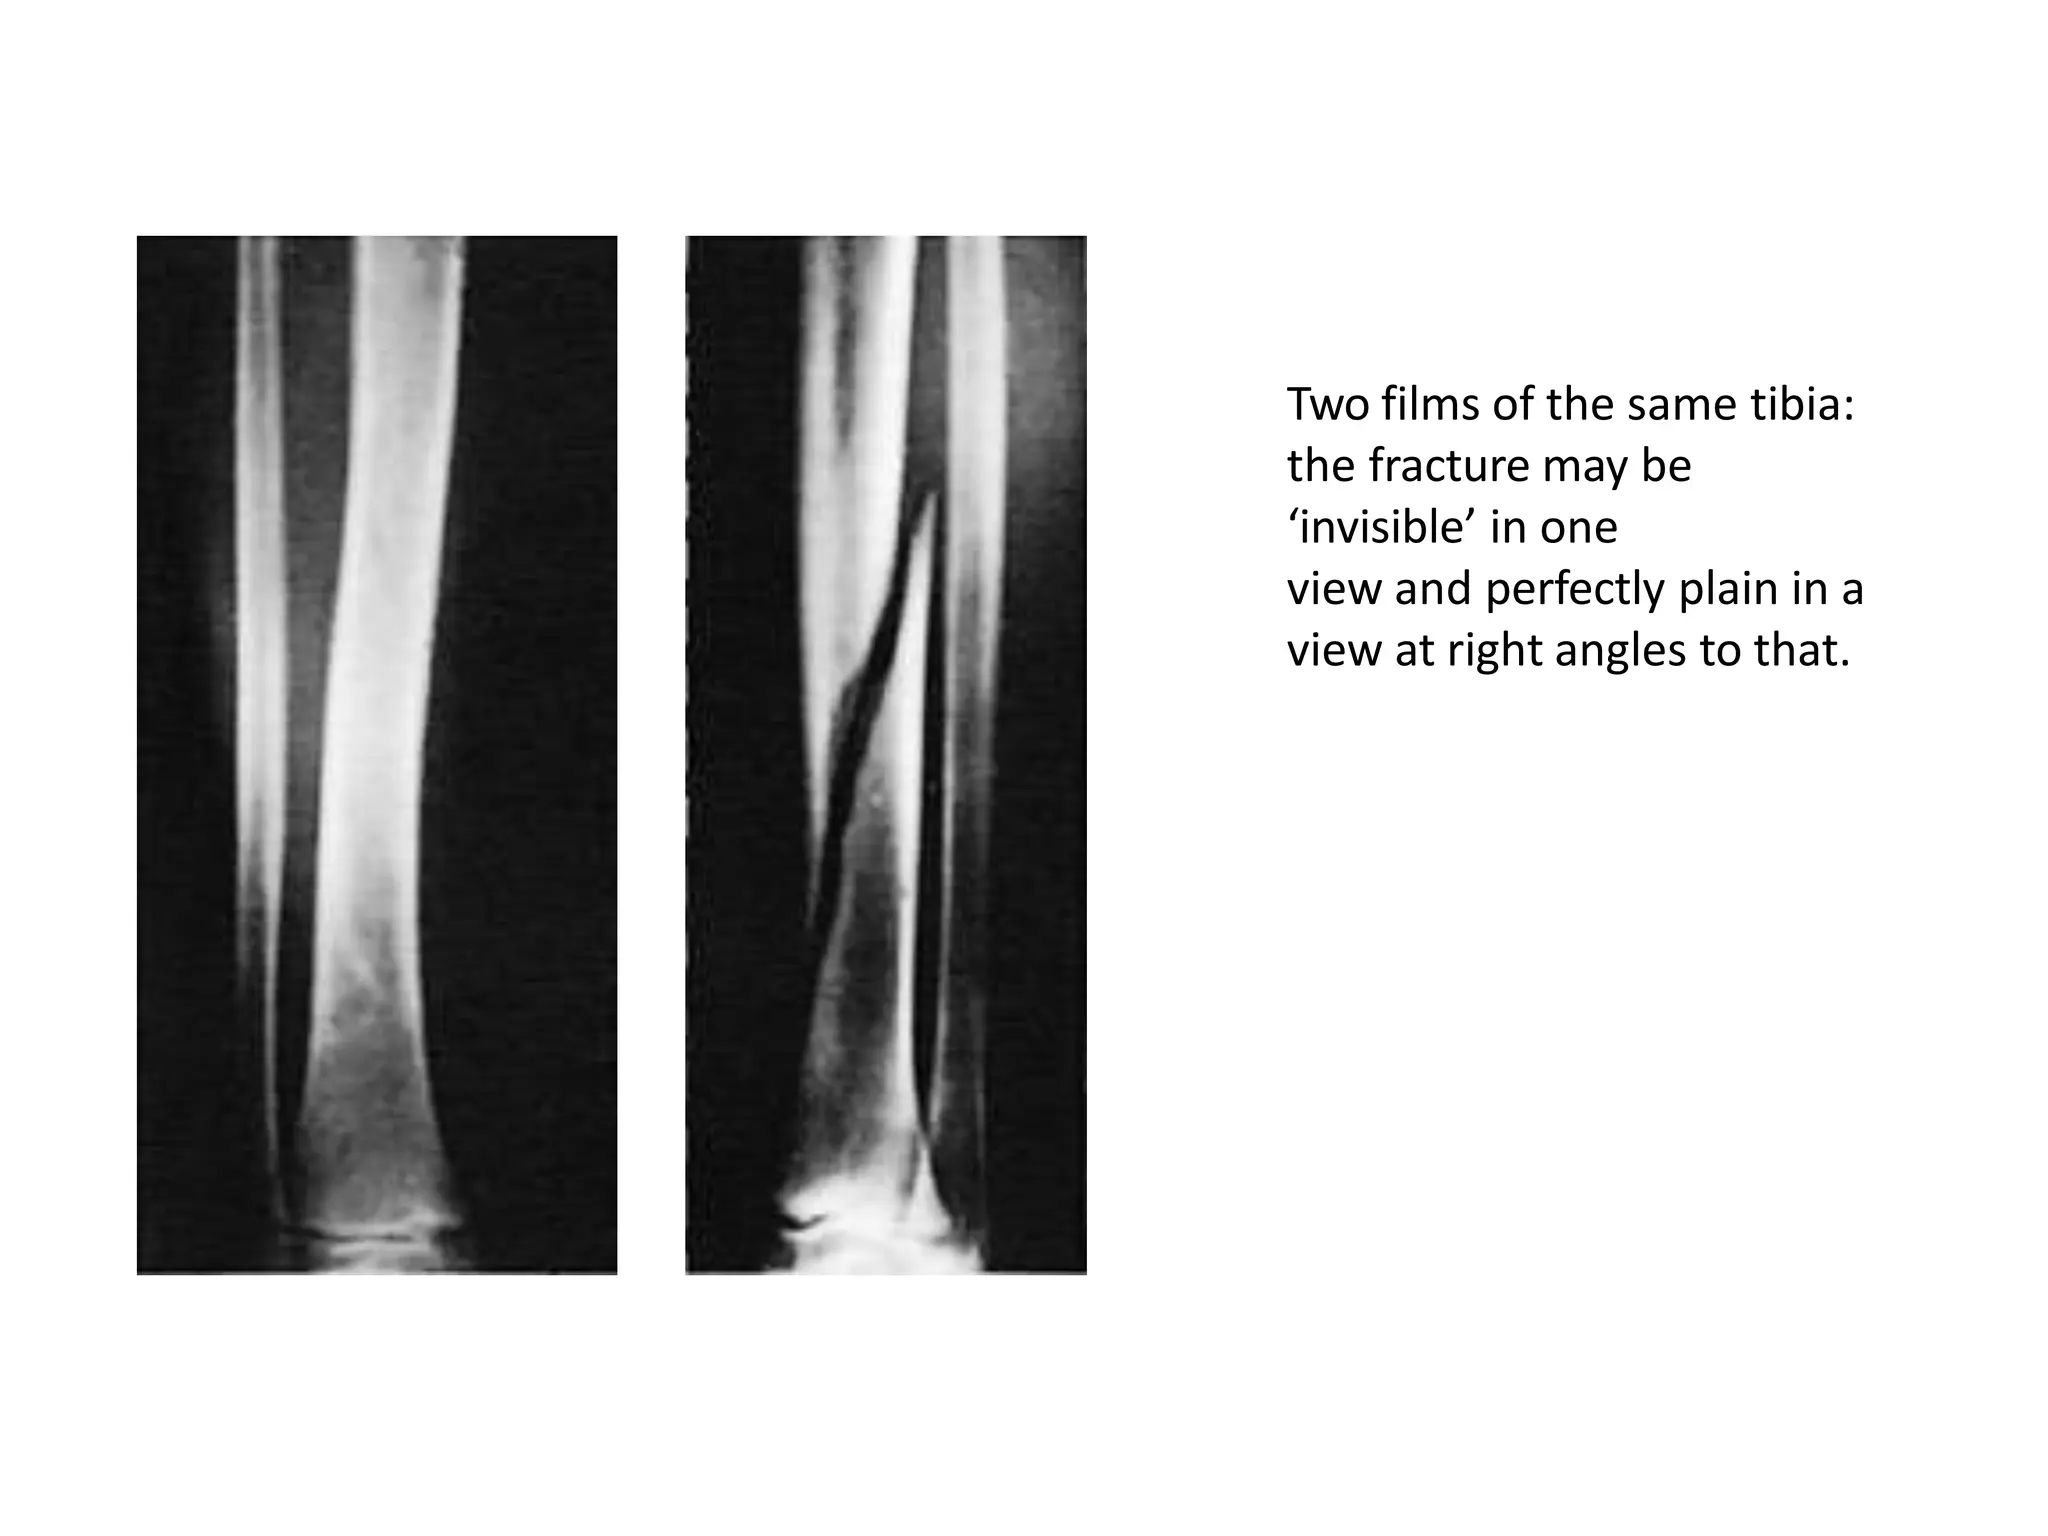

Two views – A fracture or a dislocation may not be seen

on a single x-ray film, and at least two views

(anteroposterior and lateral) must be taken.

Two films of the same tibia:

the fracture may be

‘invisible’ in one

view and perfectly plain in a

view at right angles to that.

Two films ofthe same tibia: the fracture may be ‘invisible’ in one view and perfectly plain in a view at right angles to that.